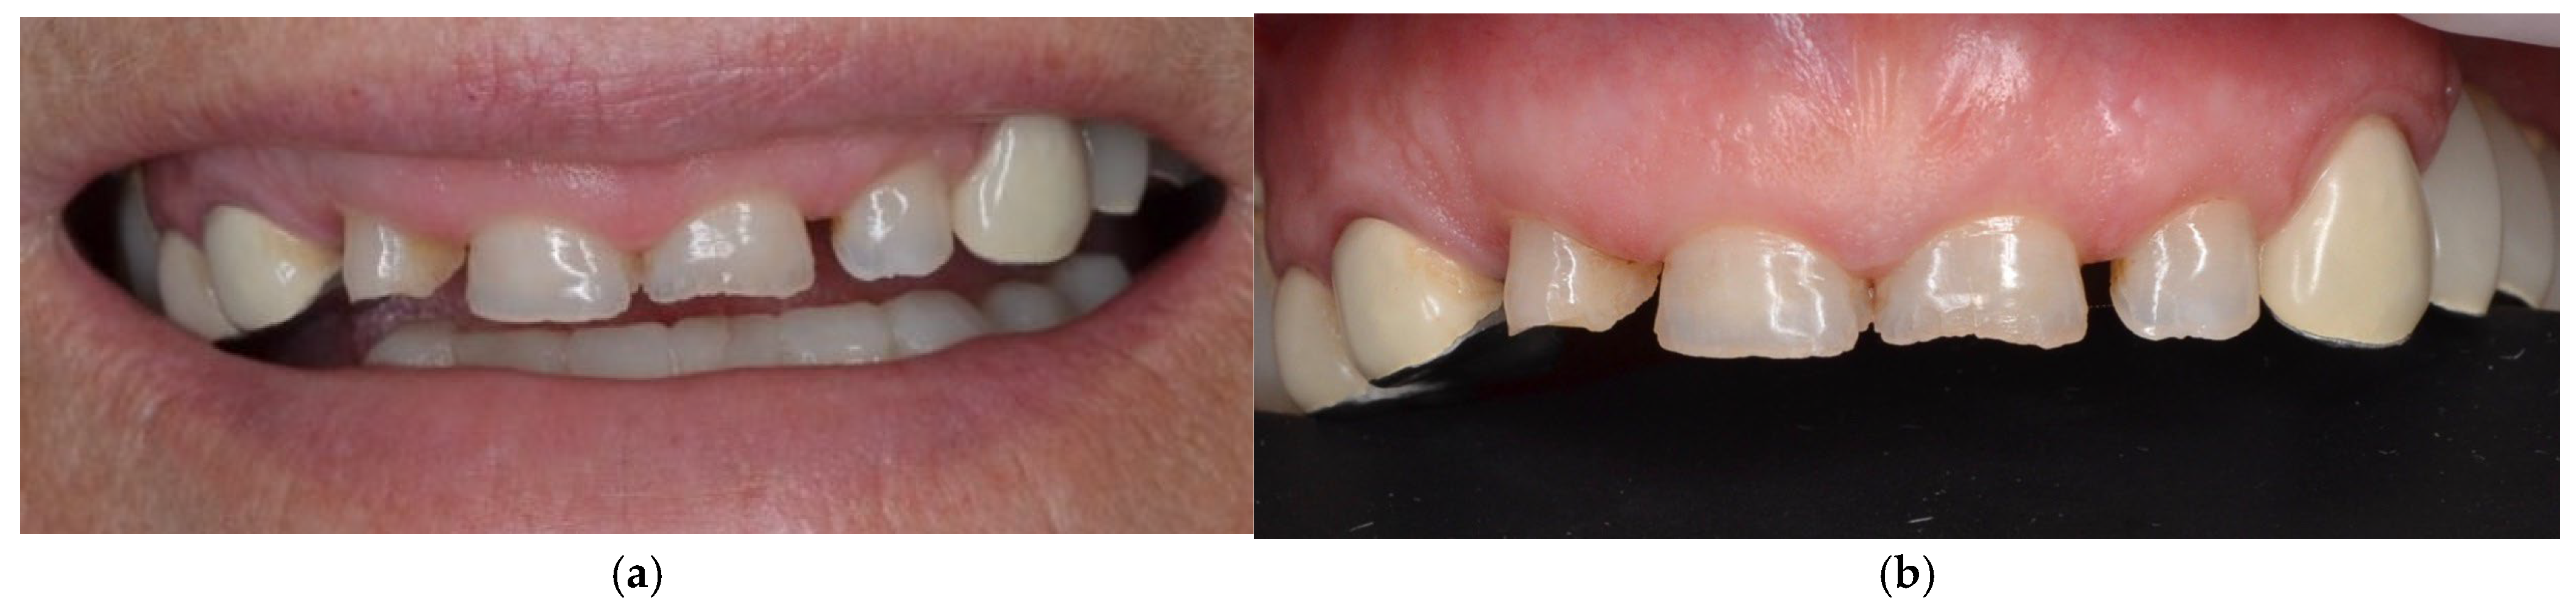

4.1. Case 1

4.2. Case 2